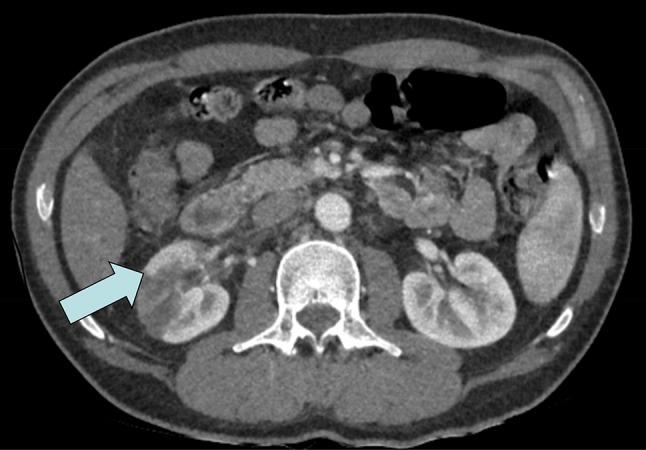

A previously healthy 45-year-old Caucasian male was admitted to the emergency room with right-sided abdominal pain, vomiting and increased frequency of voiding with no fever after a vacation in Southern Europe. Past medical history included gastroesophageal reflux which was symptom controlled with 20 mg Esomeprazole and a perforated appendectomy in childhood. He admitted to moderate alcohol consumption which increased during vacations. The condition is initially interpreted as renal colic with an ultrasound of the abdomen being reported as normal. The patient was discharged home with a single dose of Diclofenac (Non-Steroidal Anti-Inflammatory Drug); however, he returned the next day with increasing pain and a new fever (38.5 °C). A computer tomography (CT) scan was performed which revealed a right sided renal infarction affecting approximately 50% of the kidney with marked decrease contrast enhancement and a minimal surrounding edema (Fig. 1). The renal arteries were considered to have a normal appearance and there was no evidence of renal stones or hydronephrosis. The pancreas, spleen, liver, adrenals and left kidney were of a normal appearance. Chlolelithiasis without signs of chlolecystitis was also noted. The patient is subsequently admitted to the department of nephrology for further investigation. It was noted that the patient had an intense tanning of his skin and an additional investigation revealed that he had administered a total of 27 mg of Melanotan II subcutaneously within the last 6 months for the purpose of increasing his suntan. The patient self administrated Melanotan II 10 mg per injection twice within a period of 6 months and 7 mg 3 weeks before the admission to the hospital. He obtained the medication via a web shop. A sample of the drug was provided by the patient for additional investigation at a forensic center and the presence of Melanotan II was confirmed and no other pharmacologic substances were revealed in the specimen. The patient underwent investigations of the cardiovascular system including a CT-scan of the aorta, echocardiography to rule out arrhythmias and a heart ultrasound. No sources for embolus were found. Although previously normotensive, his blood pressure was recorded at 165/95 mmHg. Abnormal hematological investigations included C-reactive protein 152 mg/L, serum creatinine 102 µmol/l, blood glucose 6 mmol/L, aspartate aminotransferase (AST) 1.96 µkat/L, alanine aminotransferase (ALT) 1.23 µkat/L. Coagulative studies (international normalized ratio and activate partial thromboplastin time) and further coagulation analyses after a complementary contact with coagulation expertize revealed no abnormalities. Urinalysis by dipstick showed hemoglobin 1+. No signs for dehydration or rhabdomyolysis were found in this patient. Repeat AST and ALT were taken 2 weeks later and were reported to be within normal range. After 2 months an Iohexol-clearance-measurement was performed and showed a slightly reduced renal function (81 mL/min per 1.73 m2). The patient’s hypertension persisted and an Angiotensin-converting-enzyme (ACE)-inhibitor was introduced in the treatment. During the investigations the patient was treated with low molecular heparin, which was then stopped when all investigations were completed.

Fig. 1.

CT-scan of the right sided renal infarction